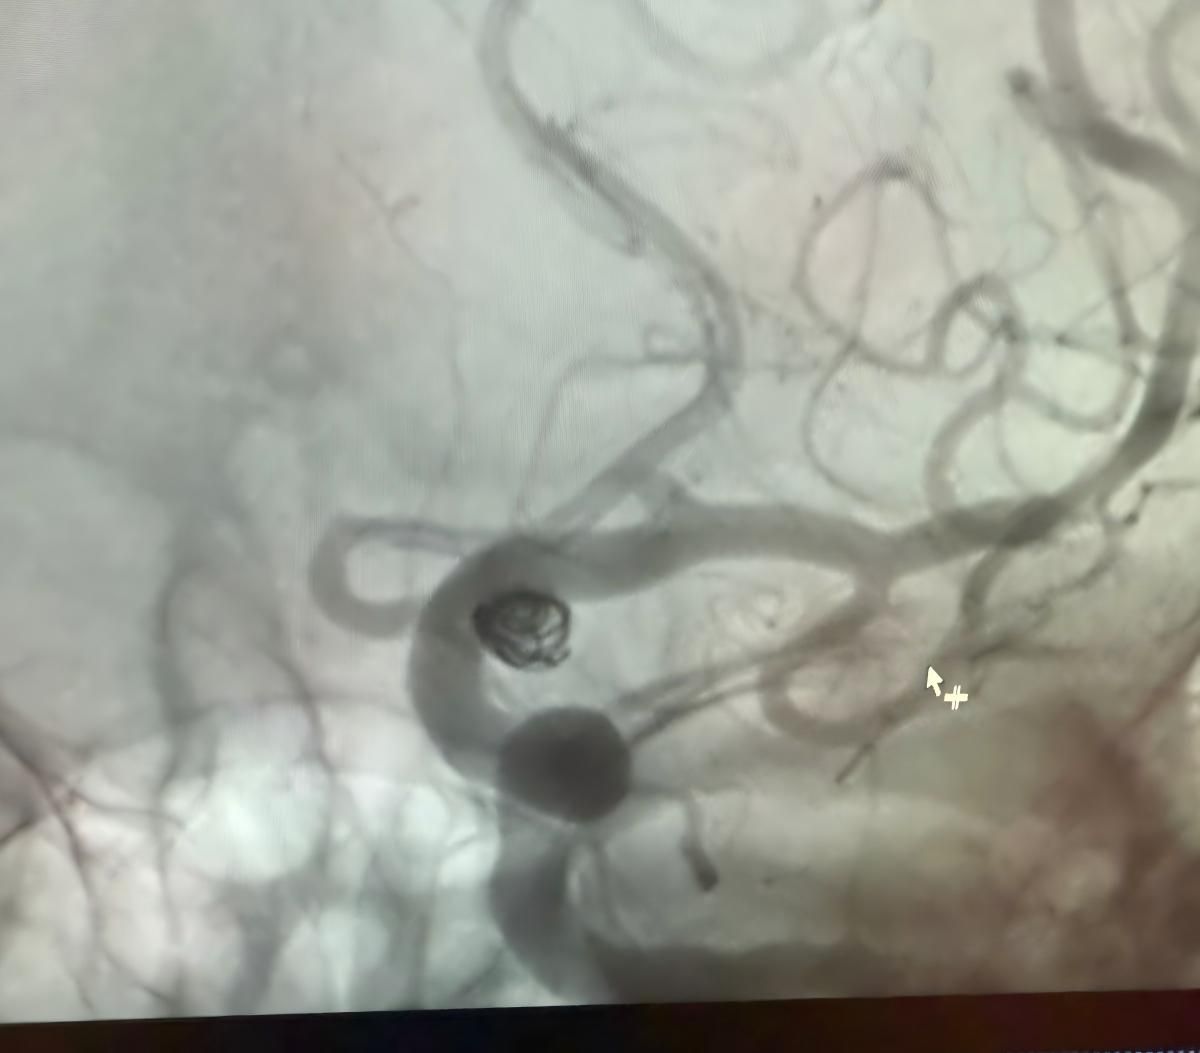

Temos o prazer de compartilhar um recente procedimento bem sucedido na Clínica Alma Mater, Medellín, realizado pelo Dr. Jorge Mutis.

O tratamento utilizou a Nuva®Desvio de fluxo (TJED-D 5.0-14), Perdenser®Bobina 3D, e Frepass®Microcateter (TJMC18 Plus) para aneurisma da artéria comunicante posterior.

O Dr. Mutis destacou a excelente visibilidade do dispositivo e observou que a recuperação foi suave. Ele expressou grande satisfação com o resultado final.